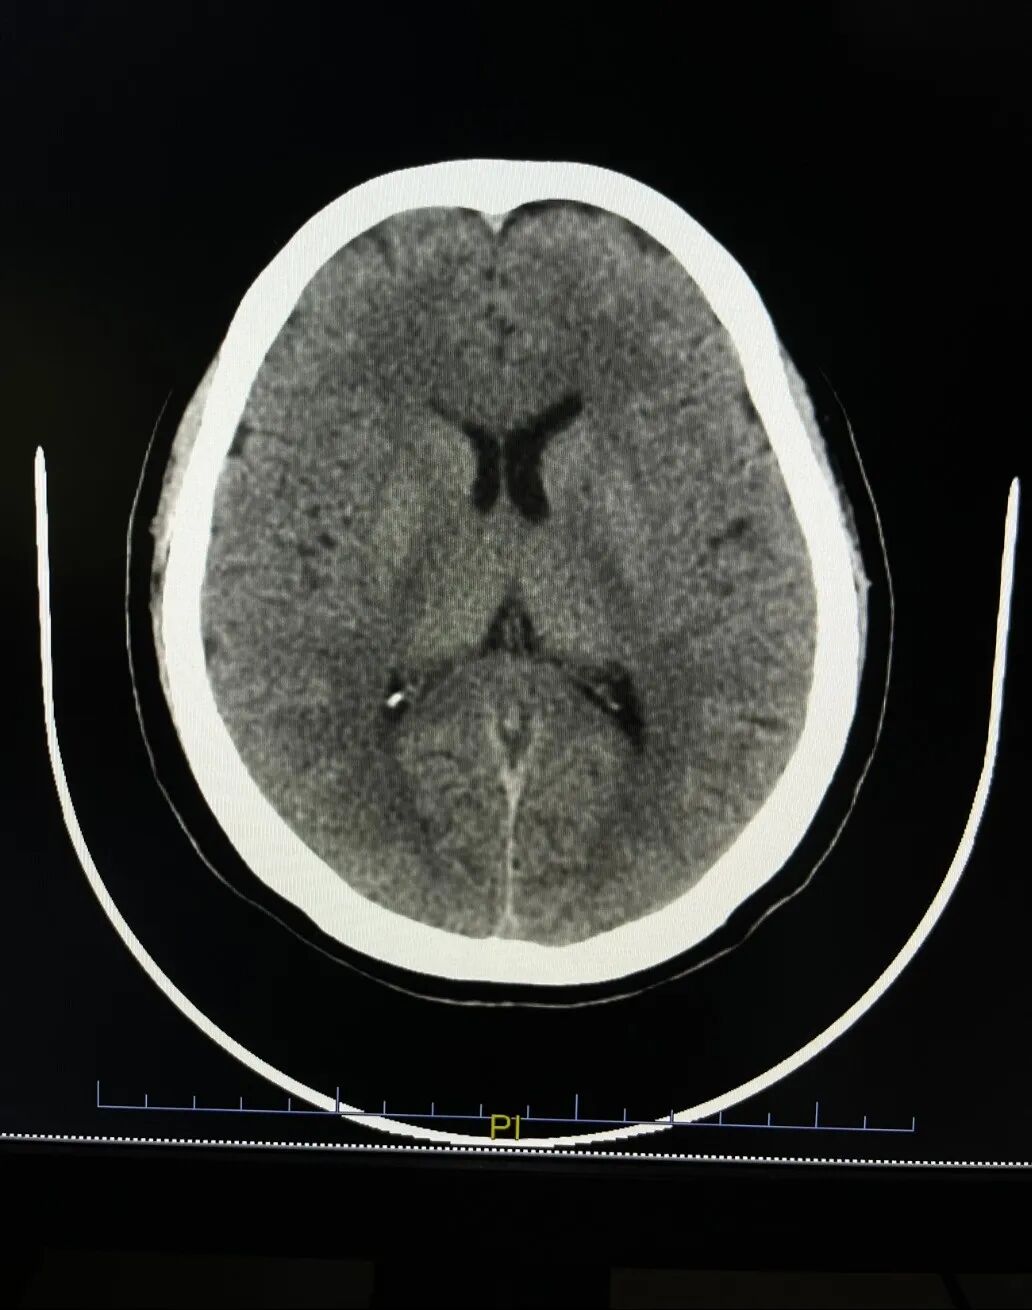

分院患者检查申请单+颅脑CT

在2022年成立了医学远程心电诊断会诊中心、影像诊断中心,初步实现“分院检查,总院诊断,医共体内互认”的目标。2024年正式落实医共体内大型医疗设备(CT/MRI/胃肠镜检查)共享机制,操作流程:医共体分院医生在分院开具大型医疗设备检查申请单,患者在分院缴费后,通过绿色通道,到总院优先安排进行辅助检查。患者只需支付一级医疗机构的检查费用就可以享受到二级医院的专业检查。分院医生可通过医共体总院系统专线查看相应检查结果,有效提高了各分院的服务质量。医共体内大型医疗设备共享解决了基层分院检查难、诊断难的问题,改善了人民群众的就医感受。